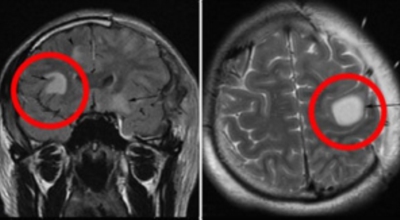

뇌출혈 전조증상을 살펴보기에 앞서 뇌출혈이란 구체적으로 무엇인지 알아보겠습니다.우리 신체의 구조상 뇌는 산소를 저장할 수 없게 되어 있어요. 그렇다면 어떻게 필요한 산소를 공급받을 수 있을까요? 우리 뇌는 산소와 영양분을 공급받기 위해 우리 몸의 구석구석을 누비는 혈관에 의존해 도움을 받습니다.

만약 이런 혈관이 파열되고, 공급되던 산소가 누출되어 뇌 조직에 도달하지 못하면 어떻게 될까요? 혈액이 고이며 뇌에 부담(압력)을 주며, 응급조치가 없이 3~4분 이상 산소가 결핍된 상태가 지속되면 뇌세포는 죽습니다. 그러면 함께 영향을 받는 신경 세포가 제어능력을 잃게 되고, 우리 몸의 기능도 함께 손상되는 것으로 보입니다.